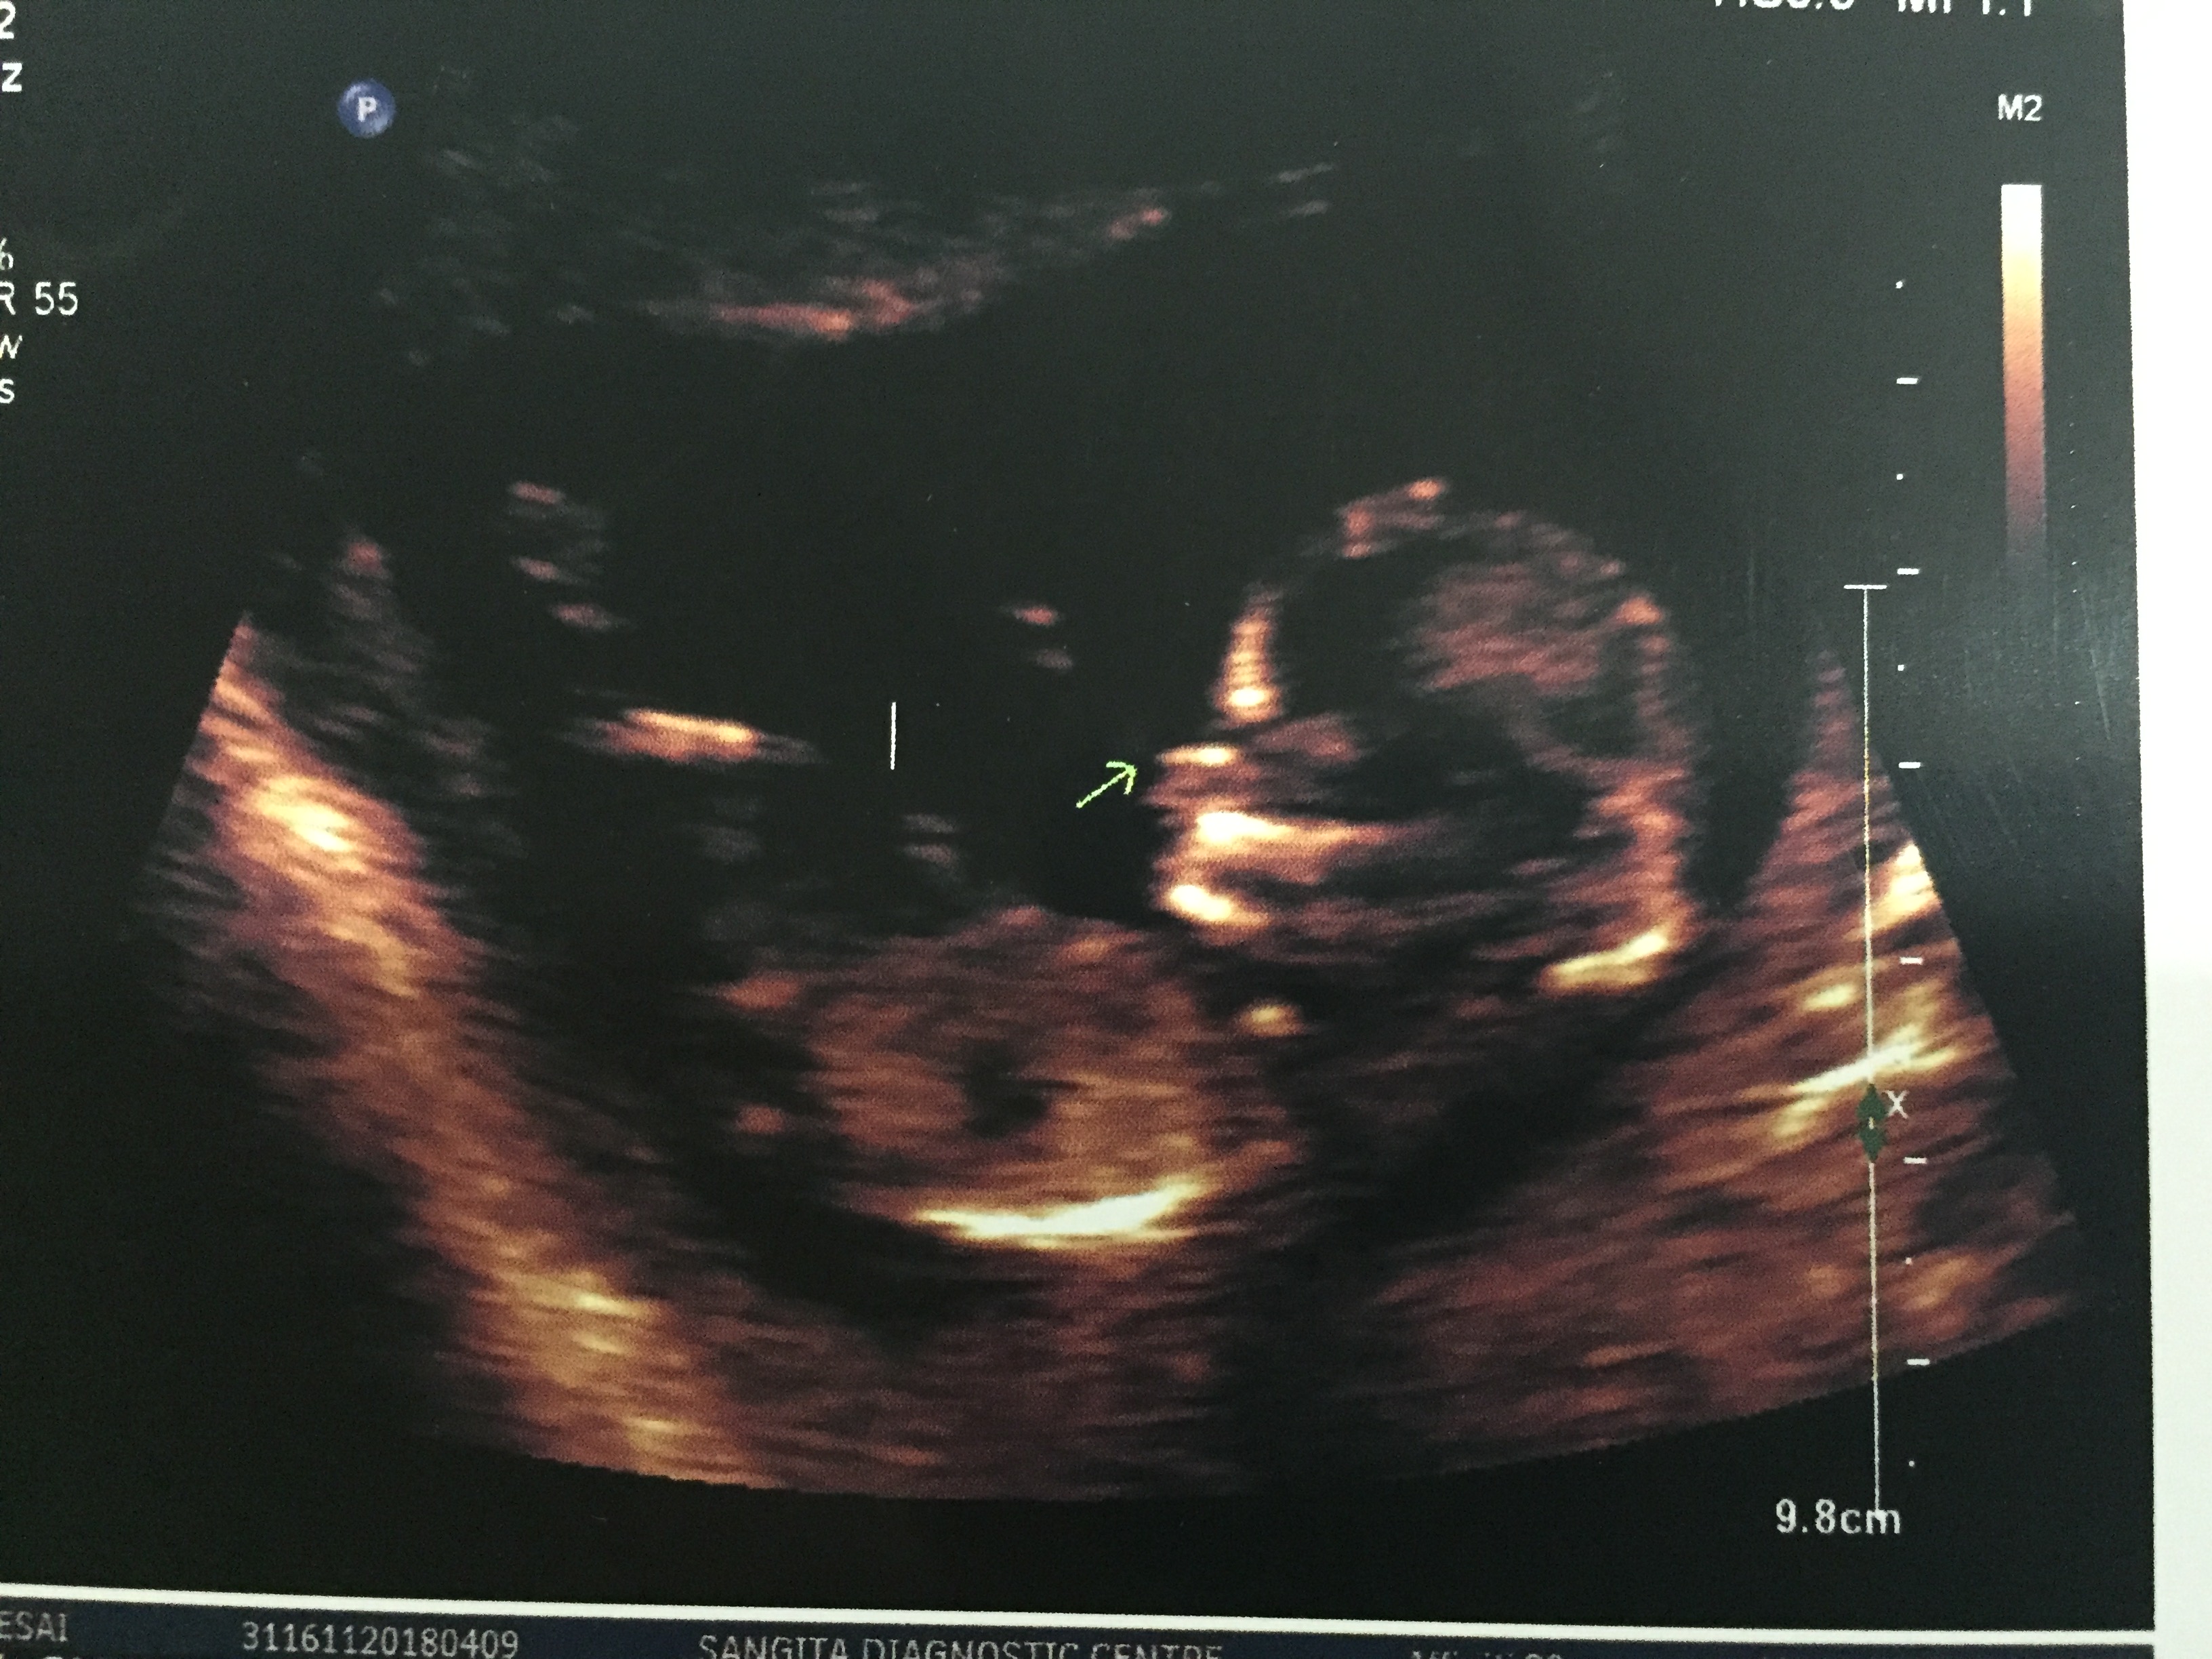

Attachment 39498Attachment 39499Attachment 39500Attachment 39501Attachment 39502

Guessing boy